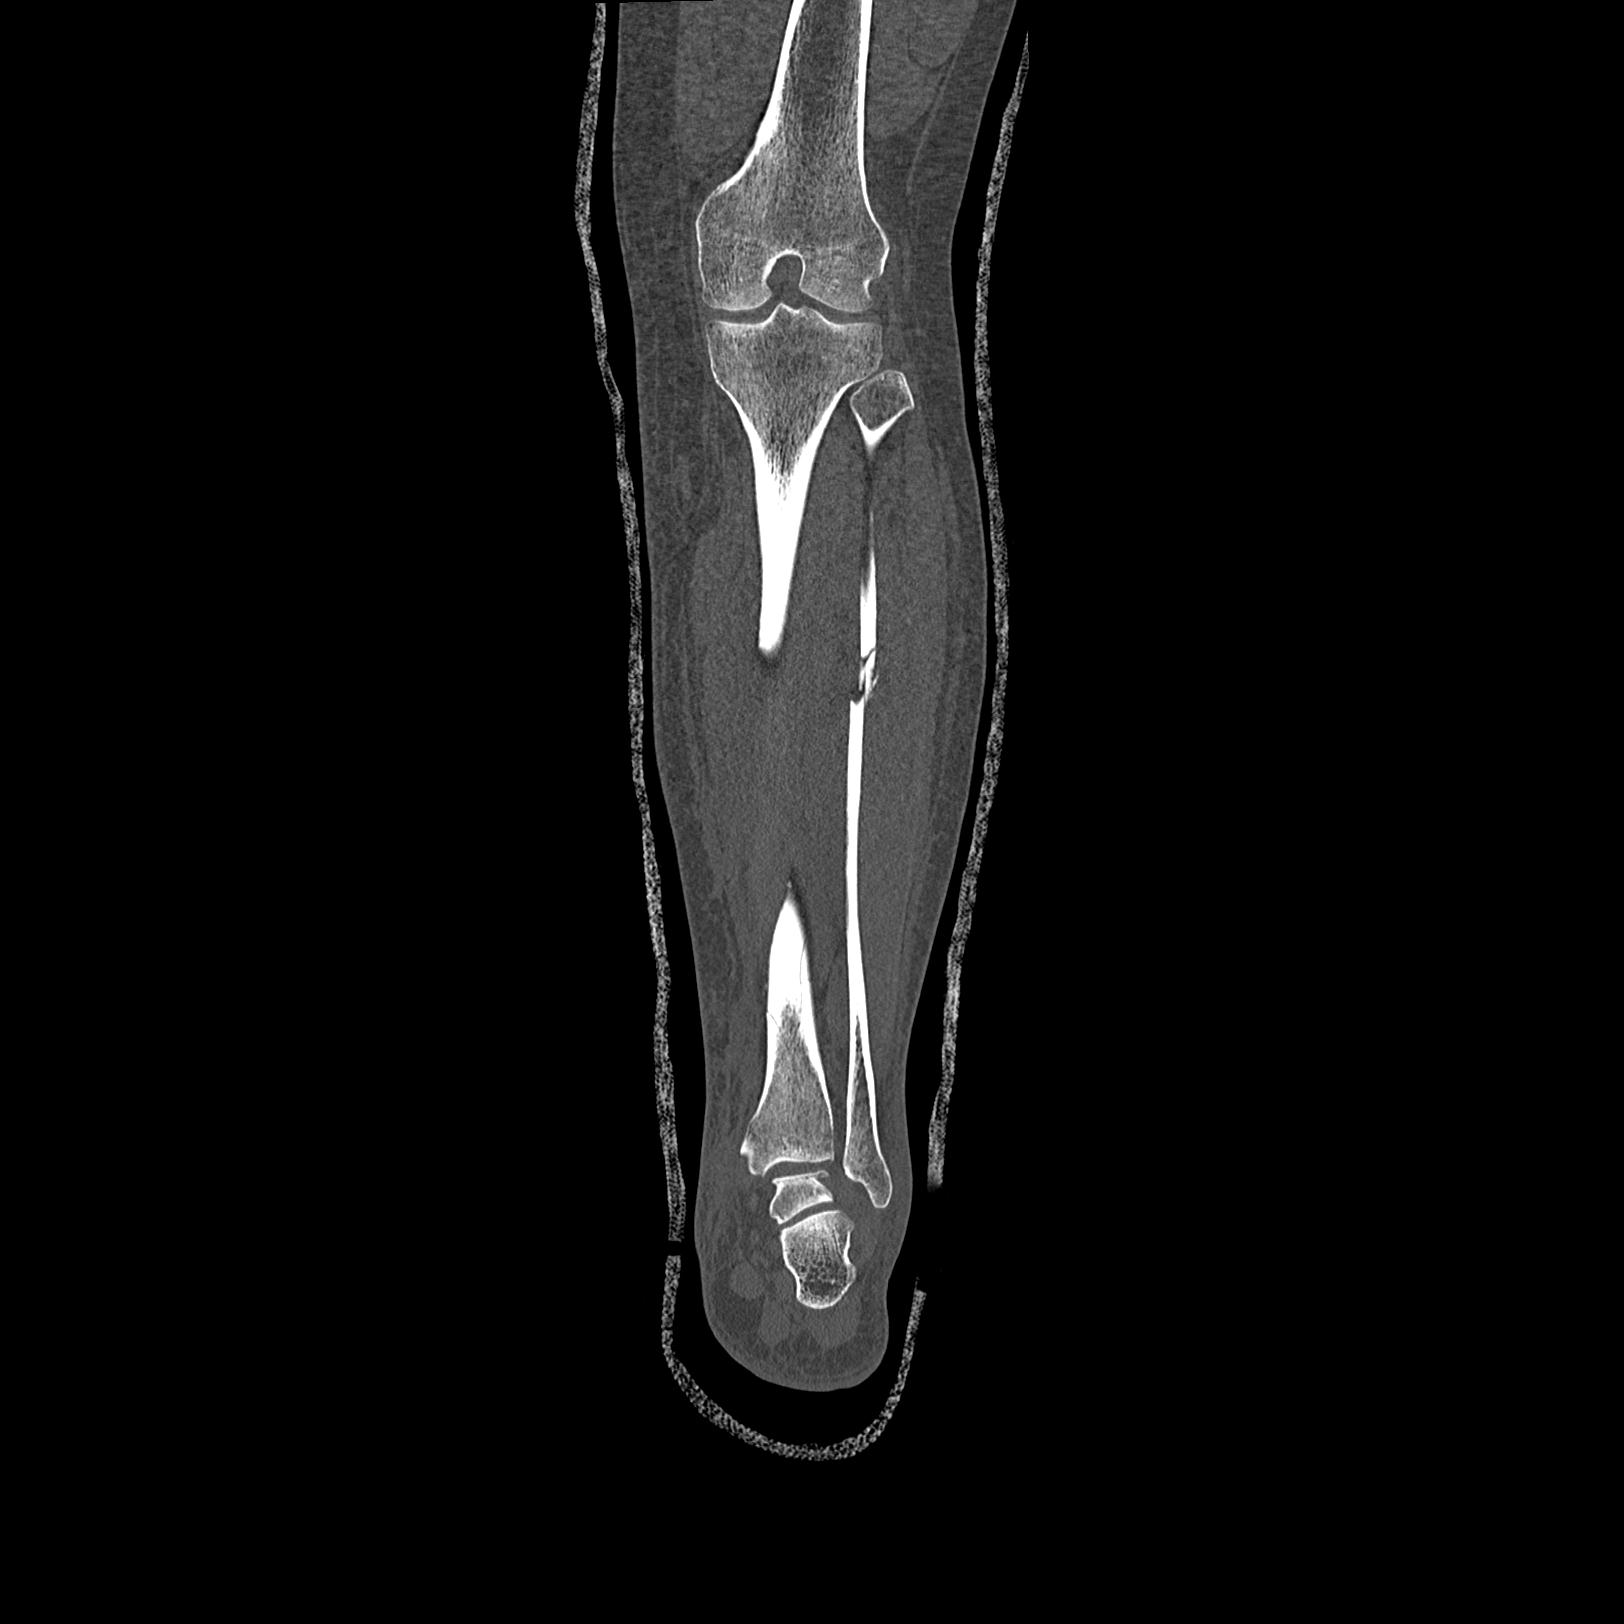

102803 1/12(キウスなし) 1/27 左下腿 4R 30歳女性 左脛骨軸内釘